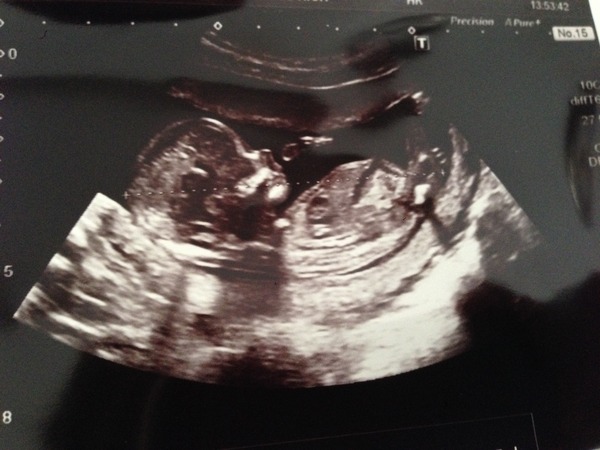

Here's my scan pic at 13+4

Brilliant pic beach really clear.

Had to go on mobile site to see scan pics. Beautiful scan pic life